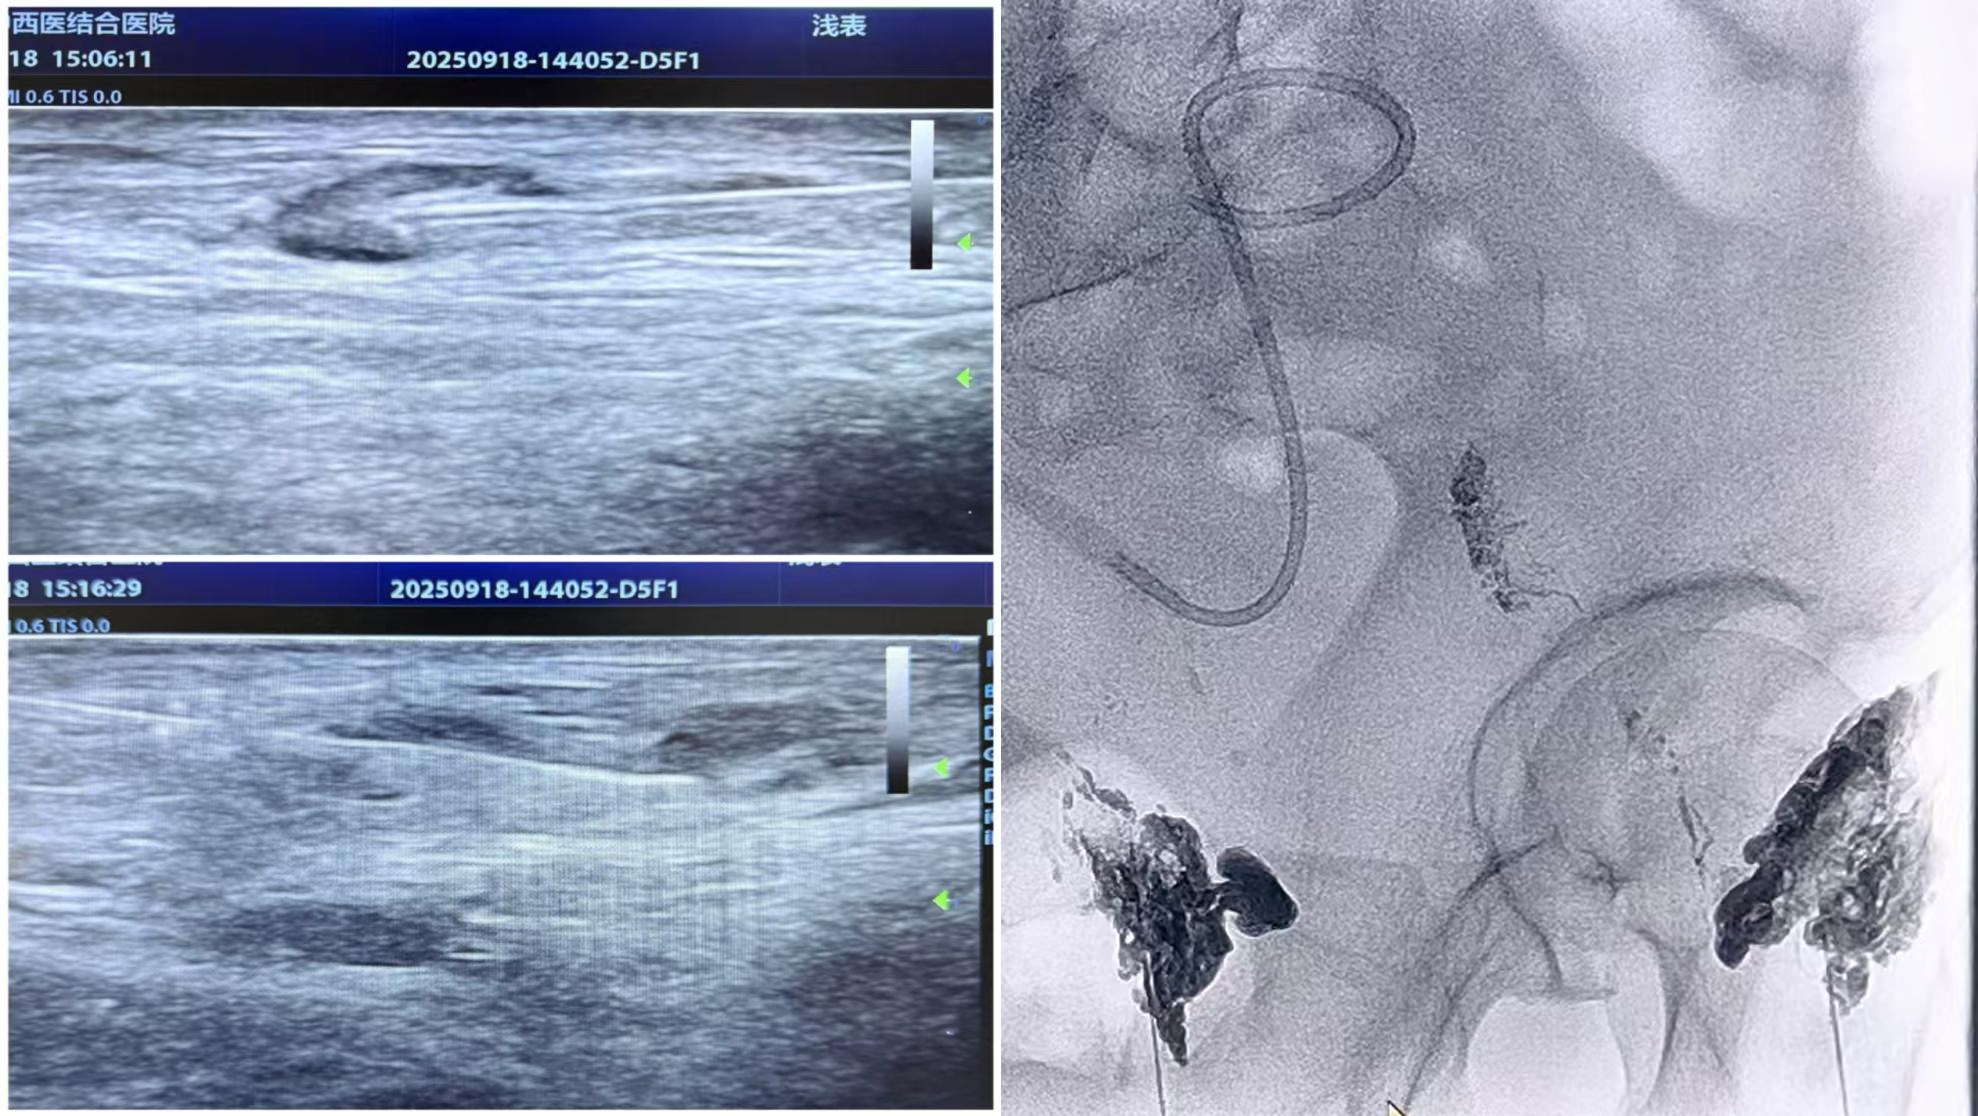

1、淋巴管精准造影:在超声实时引导下,医疗团队精准定位患者双侧腹股沟淋巴结,采用 22G 细针穿刺至淋巴结皮质与髓质交界处,缓慢注射造影剂。随后借助数字减影血管造影(DSA)技术,动态追踪淋巴液流动轨迹,精准锁定乳糜漏口位置。

2、漏口栓塞封堵:根据漏口大小与位置,选用碘油单独或与组织胶按特定比例混合,缓慢注入漏口区域,通过物理栓塞作用阻断异常淋巴液渗漏,恢复淋巴系统正常循环功能。